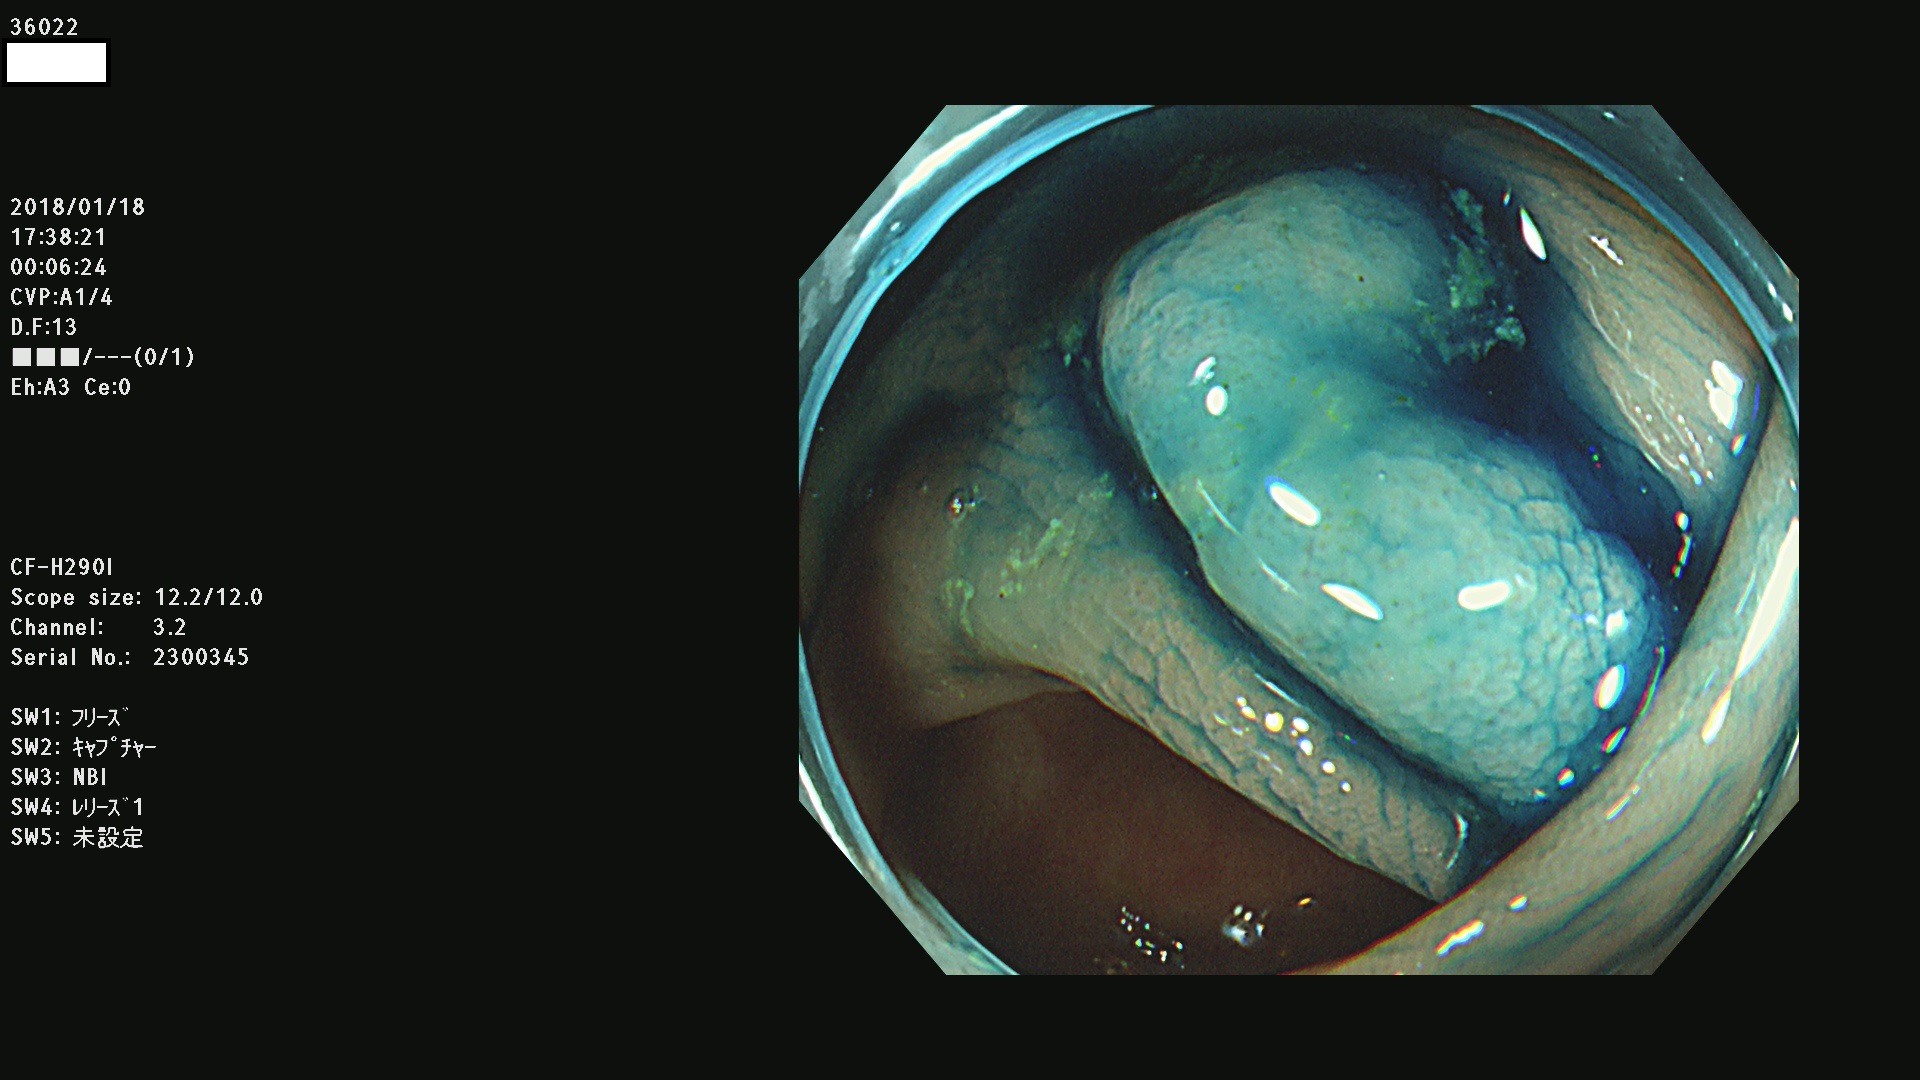

36000 36001 36003 36004 36008 36009 36012 36013(SSA/Pのみ) 36015 36016 36017 36021 36022 36023 36027 36030 36033(SSA/Pのみ) 36036 36037 36042 36044 36045 36046 36047 36051 36053 36054 36055 36056 36057 36058 36059 36060 36061 36062 36073(SSA/Pのみ) 36074 36075 36076 36078 36081 36082 36083 36089 36090(SSA/Pのみ) 36094 36096

発見困難で危険性の高い平坦型病変(上記100名より抽出)